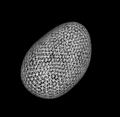

- In our recent work[1] on studying the variation of nuclear structure in tumor microenvironments [2], we have used SPHARM-PDM [3] to model 3D nuclear shape. We are interested in using itkQuadEdgeMesh as the mesh representation to this end and will be evaluating the use of this class for our system.

- Use implementation of SPHARM-PDM [3] as a starting point

- Current system for statistical shape analysis of nuclear morphology uses [3] to generate the representation

- With Arnaud Gelas, initiated work on using itkQuadEdgeMesh for generating and representing PDM for nuclei